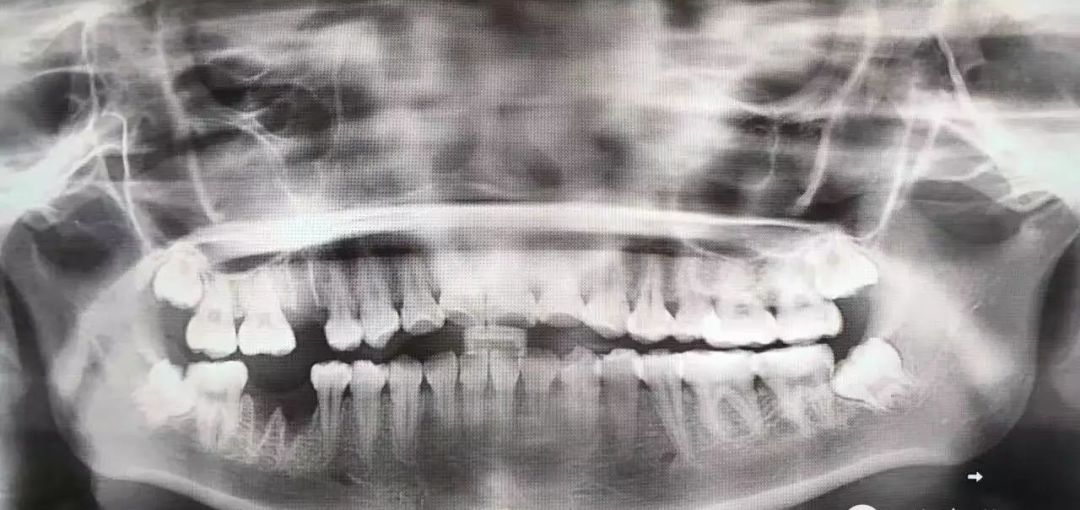

这种款式的横阻生智齿。一般生长情况也分两种,一种是已经出肉的,一种是还未出肉的,操作都差不多,我们就直接看下图的介绍了。

露出牙槽骨后,先削除一部分骨头,露出躺卧如睡美人的横阻生智齿...如果是已经出肉的智齿,就没这一步了。

请出那令人闻声丧胆的牙科涡轮机,先分割智齿,撬出块头过大的牙冠来...再把牙根磨切两半,依次撬出来。